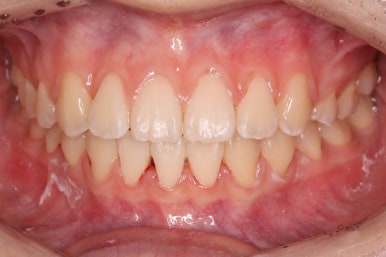

부산교정 키다리아저씨치과에서 결손치아 부분을 임플란트 하지 않고 치아교정을 통해서 개선한 이번 환자분의 치료를 마무리한 사진입니다.

치열은 가지런해졌고, 틈새는 없이 마무리되었습니다. 아랫니가 3개이지만 마치 4개인 것처럼 마무리하였고, 따라서 위~아래 치열의 중앙도 거의 맞게 마무리하였습니다.

부산교정 키다리아저씨치과에서 결손치아 치료를 마친 후의 얼굴모습입니다.

웃을 때 드러나는 치열의 모습이 매우 좋아졌고, 중앙선도 잘 맞는 것을 볼 수 있습니다. 외모를 해치지 않고 치료가 잘 마무리 되었습니다.